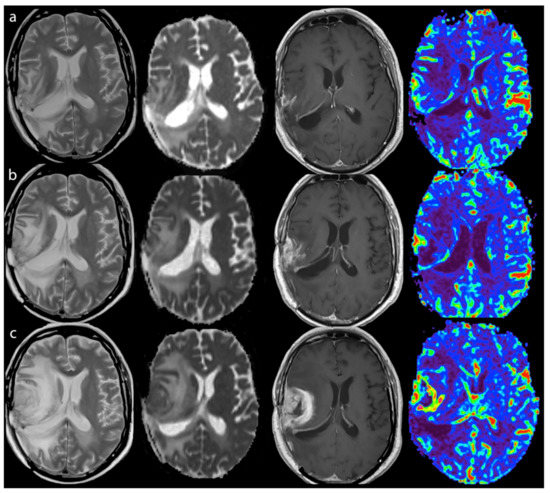

2.3.2. Perfusion

2.3.3. Diffusion

3.2.1. Response Assessment